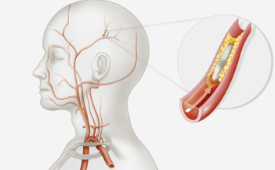

뇌경색은 뇌혈관의 벽에 지방이 쌓이게 되면서 혈관이 좁아지고, 피가 굳어 생긴 혈전이 혈관을 막게 되는데요. 이 때 뇌가 손상되는 질환입니다. 뇌경색 초기증상을 빨리 파악해야 사망률을 크게 줄일 수 있기 때문에 아주 중요합니다. 이 글에서는 뇌경색 초기증상, 뇌경색 및 뇌졸중 치료에 대한 미국 의학 협회의 지침에 대해 알아보겠습니다.

- 고콜레스테롤: LDL 콜레스테롤을 낮추고 HDL 콜레스테롤을 높이기 위한 약물과 식이요법을 시행합니다.